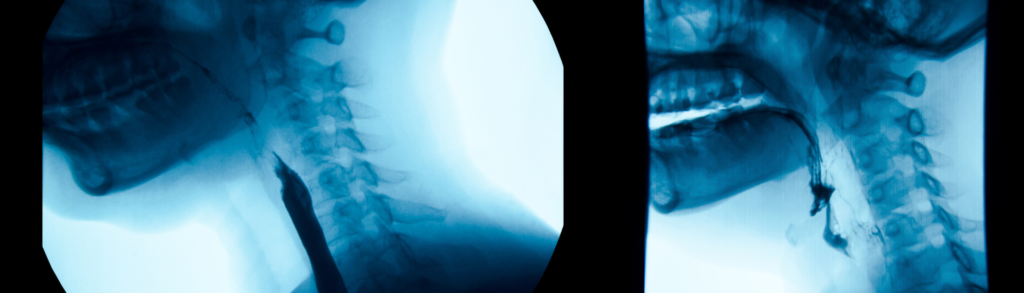

L’Esame RX Esofagogramma è un’indagine radiografica che sfrutta i raggi X combinati con un mezzo di contrasto a base di bario. Questo esame non invasivo permette di osservare la morfologia dell’esofago e di identificare eventuali anomalie o patologie. Presso il Poliambulatorio S-Medical Group di Sora, l’esame viene eseguito con tecnologie avanzate e da un team di esperti in grado di garantire sicurezza e accuratezza.

L’Esame RX Esofagogramma è una tecnica diagnostica che utilizza i raggi X per ottenere immagini radiografiche dell’esofago. Il termine “RX” si riferisce ai raggi X, mentre “Esofagogramma” indica l’immagine ottenuta. Questo esame è indicato per valutare il corretto funzionamento dell’esofago e per individuare eventuali patologie come stenosi, diverticoli, ulcere o tumori. È particolarmente utile per pazienti che presentano sintomi quali difficoltà nella deglutizione, reflusso gastroesofageo o dolore retrosternale.

Il paziente viene fatto accomodare su un lettino radiologico e gli viene somministrato un mezzo di contrasto a base di bario, che riveste le pareti interne dell’esofago. Successivamente, il paziente viene invitato ad assumere diverse posizioni per consentire l’acquisizione di immagini radiografiche complete da differenti angolazioni. Questo processo permette ai medici del Poliambulatorio S-Medical Group di Sora di ottenere una visione chiara e dettagliata della struttura dell’esofago e di rilevare qualsiasi anomalia presente.